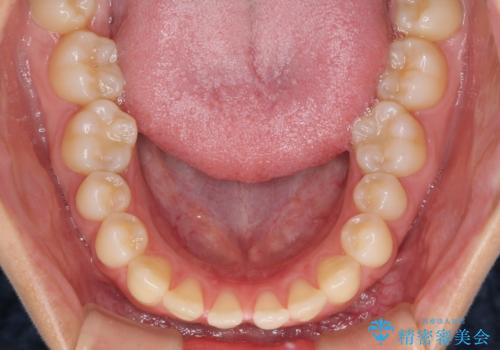

隙間だらけの歯列 インビザラインで改善

- 前歯の上下スペースと前歯の隙間を気にして来院された患者様です。

飲み込みや話をするときに舌を突出させる癖が強くあり、それが原因でスペースが空いていました。

舌癖を改善するためのトレーニングを行いながら、インビザラインにより上下の前歯の隙間を閉じていくこととしました。